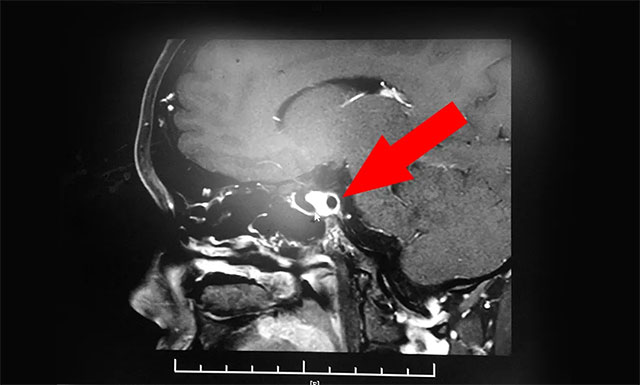

▲ 患者确诊为蝶窦囊肿

潘仁龙主任根据小萌当时所述病症,并结合其病史及鉴别诊断,判断其颅内鞍区可能存在器质性病变,随即对患者进行了鞍区MRI平扫+增强,结果显示患者腺垂体和神经垂体形态如常,腺内未见占位性病变,但在蝶窦部发现蝶窦性囊样灶、囊壁和分隔富血供,最终诊断为蝶窦囊肿。